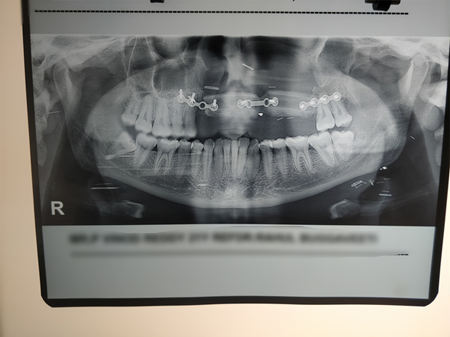

OPG shows osteotomies of fibula(reshaped leg bone)